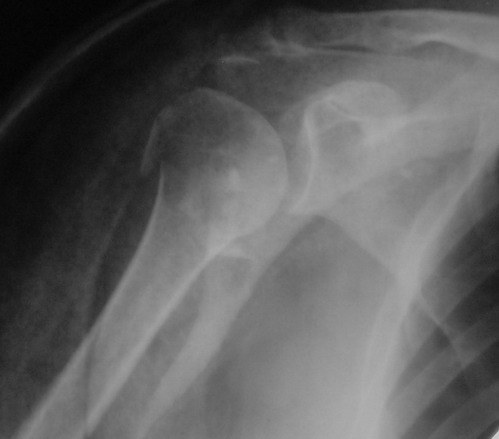

Снимки на 1-е сутки после репозиции и на 8- сутки после репозиции.

Никто не отменял функционального консервативного метода лечения. Дело не только в том, что перелом сросся, вопрос в каком положении.

При переломах хирургической шейки плеча ротаторная манжетка ротирует фрагмент головки внутрь, поэтому при неустраненном упомянутом смещении

перелом рано или поздно срастется, но отведение плеча будет страдать. Очень практичен и функционален метод А.Ф. Лазарева, о котором упомянул Джолдас, ранее обсуждался на форуме , попробуйте, больные будут довольны

На 20-е сутки снял гипс, одел фиксирующюю

ортопедическую повязку. Вот контроль. Как видно, стояние хорошее, уже формируется костный мозоль.

Думаю еще недели 3 продолжать фиксацию.

-Головка плеча в небольшом варусе или это

проекционное?

Да, там имеем небольшой варус, надеемся, что в будущем проблемы не будет.